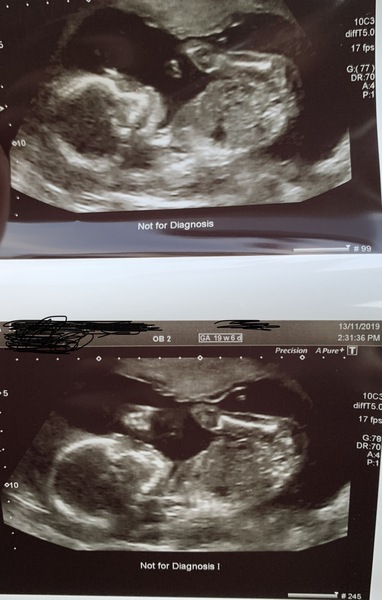

jl2345 · 16/11/2019 08:35

Also these are the photos, look at its little hand in the bottom one 🙊

Due March 2020 - FIRST BABY in late 20's

@jl2345 awwww he's saying hello! 🥰🥰🥰